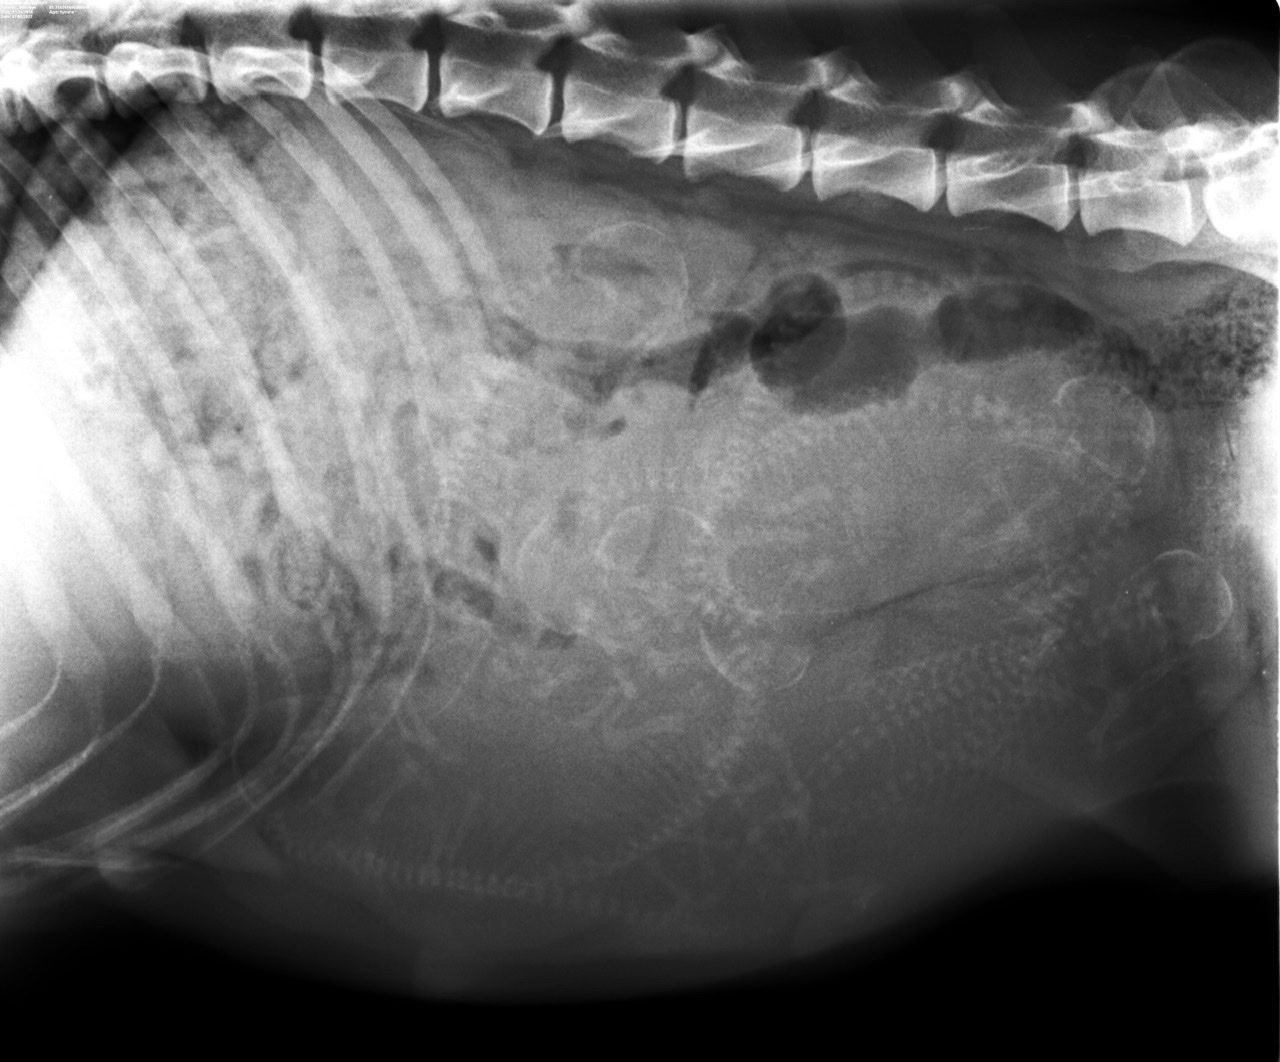

Radiographie des chiots

Mise à jour du 5 juillet 2022

Millesys avait rendez-vous aujourd’hui chez notre vétérinaire pour une radiographie de la portée. Millesys a pris 6 kilos ; elle a tout le temps faim, ce qui nous change de sa précédente portée durant laquelle il fallait la forcer à manger ! la gestation se passe très bien.

A vos pronostics !

Nous prenons la route et arrivons vers 2 heures du matin. A l’examen, la vétérinaire pense que l’utérus ne se contracte pas pour expulser les chiots et diagnostique un cas de dystocie. A l’échographie, les coeurs des chiots battent mais sont trop lents en rythme. Il y a souffrance foetale. Une radio montre qu’un chiot est déjà engagé et qu’il bloque le passage. Décision est prise de faire une césarienne. Le chirurgien est appelé chez lui pour l’opération et arrive une demi-heure plus tard à la clinique. Commence une longue attente dehors, sur le parking de la clinique vétérinaire qui nous paraît interminable.